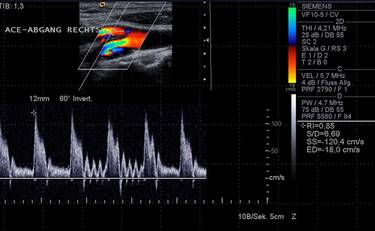

Der Vorteil der Ultraschalluntersuchung gegenüber anderen bildgebenden Verfahren ist die  fehlende Strahlenbelastung sowie die schnelle Verfügbarkeit und Wirtschaftlichkeit. Im Kopf-Hals-Gebiet steht die hohe Auflösung feiner oberflächennaher Strukturen im Vordergrund, die mit modernen Geräten heute schon fast an den mikroskopischen Bereich heranreichen. Klassisches Anwendungsgebiet der Ultraschalluntersuchung ist die Nachsorge bei Tumorpatienten und die Diagnostik von Veränderungen der Speicheldrüsen. Routinemäßig erfolgt zusätzlich die Untersuchung der Schilddrüse, des Mundbodens und der großen Gefäße im Halsbereich.

Eine vollständige Ultraschalluntersuchung und Dokumentation im Kopf- und Halsbereich kann bis zu 30 Minuten dauern. Für krankhafte Veränderungen gibt es momentan kein besseres diagnostisches Verfahren als die Sonographie. Dies gilt umso mehr, je näher der Befund bzw. die Veränderung an der Körperoberfläche gelegen ist. In der Hand des geübten Diagnostikers übertreffen die Ergebnisse der Sonographie die der Computertomographie.